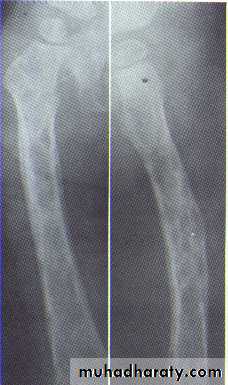

Histiocytosis-X (Langerhans cell disease):They are three manifestations produce tumour-like lesions in bone, caused by proliferation of Langerhans cells and eosinophilic leucocytes.

Radiographically :

• Multiple radiolucent areas in the interdental & interradicular bone.

• teeth seem to hang in air. Exfoliation of teeth & teeth germ are common, ulceration of overlaying mucosa.

• Multiple radiolucent foci seen in the skull & long bone of the skeleton, lesion in the skull give appearance of geographic map , with skull enlargement .

• Histiocytosis-X

• Eosinophilic Granuloma (2nd-3rd decade of life).• Hand-Schüller-Christian disease (1stdecade of life).

• Letterer-Siwe disease (before 2 years of age).